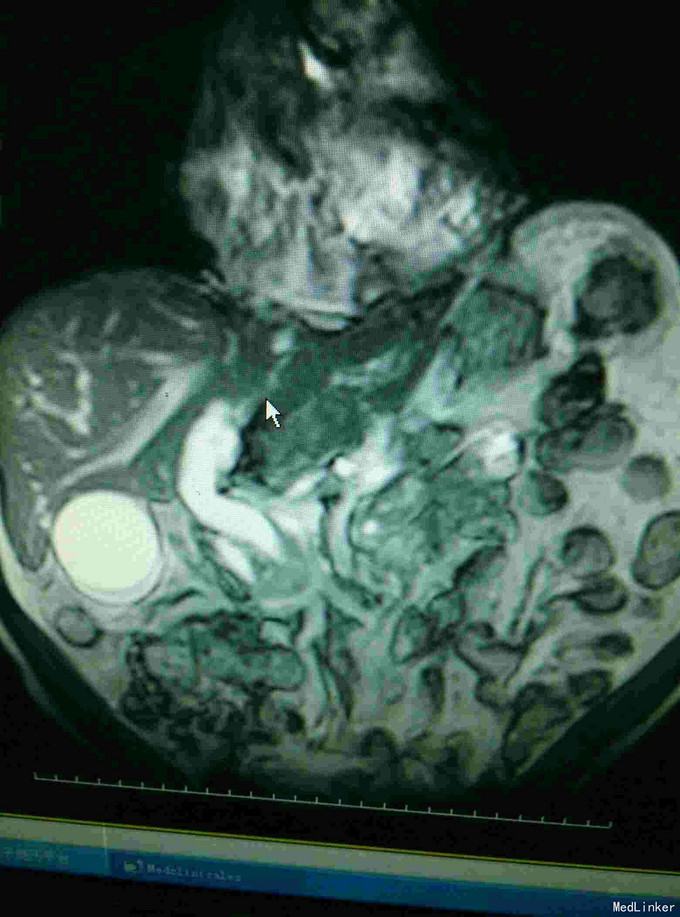

男患,74岁“发现全身皮肤及黏膜黄染2周”,2周前发现皮肤黄染,伴有纳差、厌油,无明显皮肤瘙痒,无发热、寒战,无恶心、呕吐,大便稍稀,无明显白陶土样大便,小便颜色基本正常。

全身皮肤黄染,虹膜黄染,心肺未见异常,腹部稍膨隆,肝区轻度扣击痛,Murphy症阴性。腹部查体腹部B超提示:肝内外胆管扩张,胆囊结石,胆总管下端可见低回声团。MRI如下:

梗阻性黄疸,择日进行了“胆囊切除,胆肠吻合术”,术中见胆囊及上段胆总管明显扩张,下段胆总管塌陷。